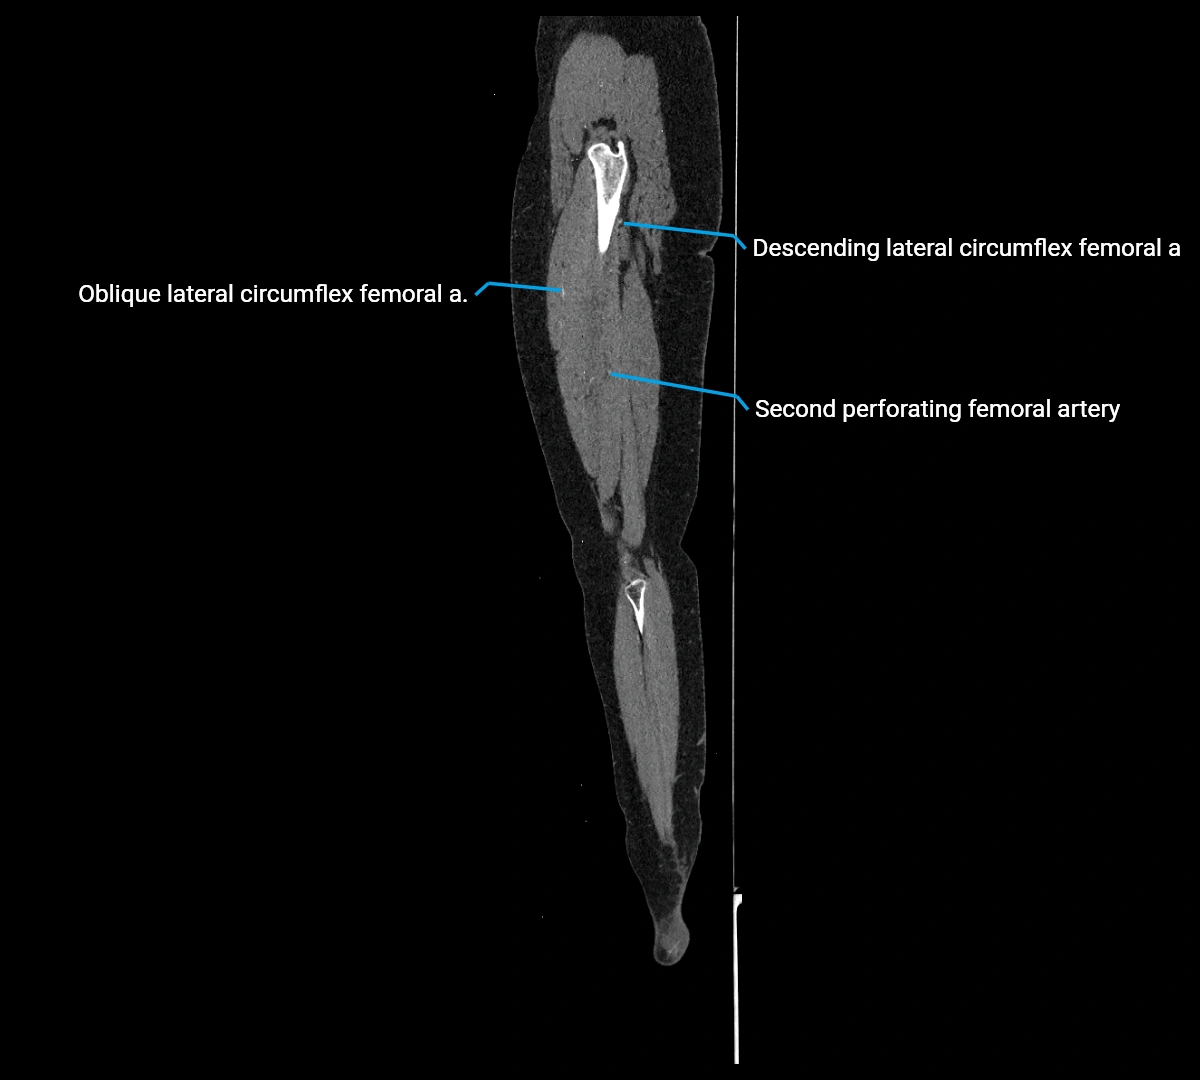

CT images

image

Contrast-enhanced CT (CTA):

• Gold standard for abdominal aortic imaging

• Provides excellent detail of lumen, wall, aneurysm, thrombus, and branch vessels

• Multiplanar and 3D reconstructions help in aneurysm measurement, stent graft planning, and dissection evaluation